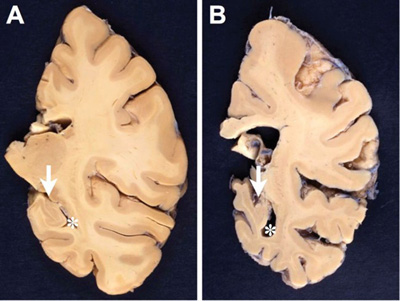

The AD brain often has decreased weight and at least moderate cortical atrophy most marked in the medial temporal lobes (MTLs) with relative sparing the primary motor, somatosensory and visual cortices and enlargement of the lateral ventricles (ex vacuo hydrocephalus). Brain atrophy often involves posterior cortical areas, most notable in precuneus and posterior cingulate gyrus in the preclinical stage of AD [28]. However, none of the macroscopic features are specific to AD, and healthy elderly people often show moderate cortical atrophy especially affecting the frontal lobes, with volume loss of the white matter [29]. Medial temporal atrophy affecting amygdala and hippocampus with enlarged temporal horn is typical of AD (Fig. 1). However, this is also seen in other age-related disorders such as hippocampal sclerosis [30].

Figure 1. Comparison between formalin-fixed brain slices of the left hemispheres (level of posterior hippocampus) of an aged nondemented individual (A) and an AD patient (B). Note the marked atrophy (thinning of the gyri and deepening of the sulci) in B, in particular hippocampal atrophy (arrow in B) with widening of the inferior horn of the second ventricle (asterisk in B). Photographs by courtesy of Simon Fraser and Arthur Oakley.